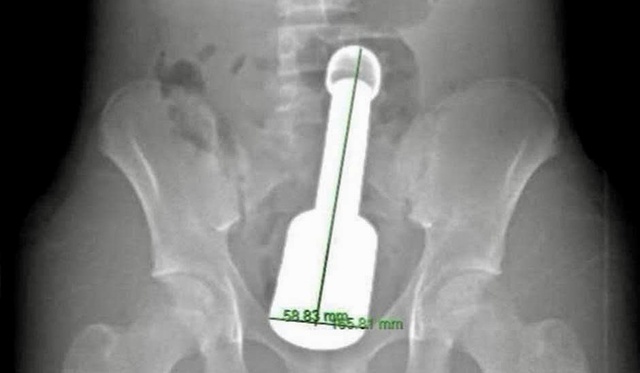

Hình ảnh chiếc chày kim loại dài 18 cm, đường kính 6 cm mắc kẹt trong hậu môn bệnh nhi

Sau hơn 45 phút, dị vật là chiếc chày kim loại dài 18 cm, đường kính 6 cm đã được lấy ra hoàn toàn qua đường hậu môn.

Chiếc chày không chỉ to (đường kính 6 cm, là giới hạn cực đại đối với cơ thắt hậu môn của một thiếu niên) mà còn rất nặng và tạo ra "hiệu ứng chân không" phía trên đỉnh dị vật, khiến nó bị hút chặt vào lòng ruột.